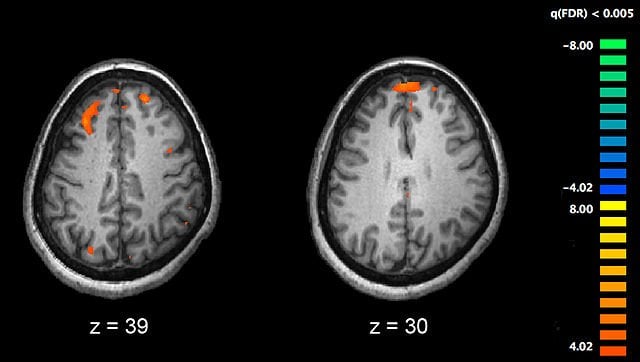

Schizophrenia fMRI brain scans are shown.

New de novo Genetic Mutations in Schizophrenia Identified

Columbia University Medical Center (CUMC) researchers have identified dozens of new spontaneous genetic mutations that play a significant role in the development of schizophrenia, adding to the growing list of genetic variants that can contribute to the disease. The schizophrenia study was the largest and most comprehensive of its kind.